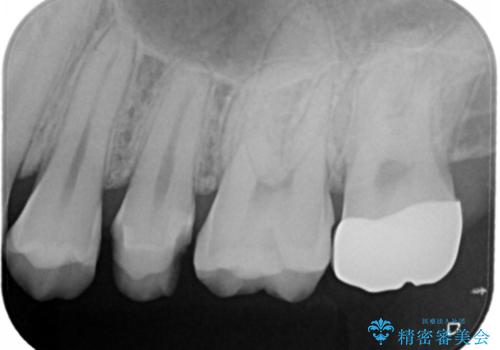

奥歯を治療したい フルジルコニアクラウン

- 99000円(フルジルコニアクラウン+仮歯)費用は治療当時の料金となります